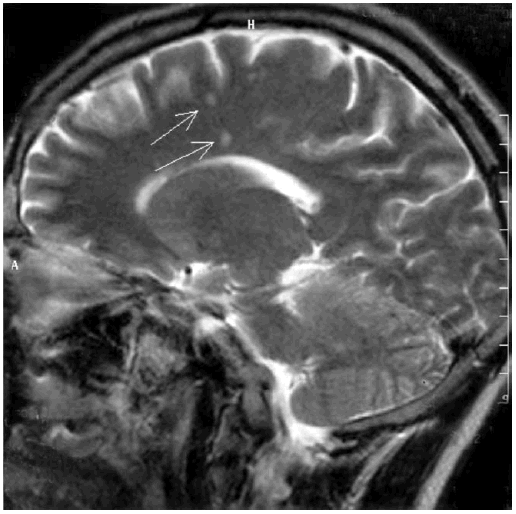

Спустя семь лет было установлено, что эпидемическая вспышка в городе Лайм была вызвана особым возбудителем, которого назвали боррелией, а заболевание – болезнью Лайма, или клещевым боррелиозом. Болезнь распространена не только в США (в 2001 г. зарегистрировано 17 029 случаев), но и в европейских странах (ежегодно около 60 тыс. случаев), в том числе в России. При клещевом боррелиозе через 2–4 недели от присасывания клеща у 40 % пациентов в Европе и у 80 % больных в США возникают кожные проявления. Обычно это кольцевидная эритема, одно или несколько красных пятен в месте присасывания клеща, подъем температуры тела, головная боль, тошнота. Нам приходилось наблюдать и диссеминированные формы. Позднее может развиваться серозный менингит, поражение лицевого нерва, ухудшение зрения, боли в области суставов, сердца. Необходимы срочная госпитализизация в остром периоде, проведение антибактериальной терапии по поводу клещевого боррелиоза, тогда полное выздоровление наступает у 70 % больных. Нередко клещ является носителем клещевого энцефалита и клещевого боррелиоза одновременно. После укуса клеща высока вероятность заражения клещевым боррелиозом (в природных очагах 20–50 % клещей – носители боррелий). Опыт сотрудников кафедры инфекционных болезней Военно-медицинской академии по профилактике и лечению клещевого боррелиоза изложен в книге «Лайм-боррелиоз (иксодовые клещевые боррелиозы)» Ю. В. Лобзина, А. Н. Ускова, С. С. Козлова [110]. Если от момента укуса клеща прошло меньше трех суток, рекомендуют антибиотик доксициклин в дозе 0,1 в таблетках один раз в день в течение пяти дней (можно детям старше восьми лет); если этот временной период превышен, то профилактический курс следует продлить до десяти дней. Такой подход позволяет предупредить развитие клещевого боррелиоза и переход его в хронические формы заболевания. Вопрос о хроническом клещевом боррелиозе в настоящее время широко обсуждается. Доказано, что Borrelia burgdorferi может персистировать в нейронах и глиальных клетках длительное время. При этом пенициллин, цефтриаксон, доксициклин не обладают эффективностью против этих бактерий в хронической форме, когда они представлены в виде цист [321]. У пациентов с множественными очагами демиелинизации по данным МРТ головного мозга выявляются когнитивные расстройства [290]. Приводим МРТ головного мозга пациента 37 лет с нейроборрелиозом, у которого развилась картина умеренной деменции (рис. 9.2).

Иллюстрация к книге — Деменция. Диагностика и лечение [i_008.jpg]

Рис. 9.2. МРТ головного мозга пациента с нейроборрелиозом. Множественные очаги демиелинизации